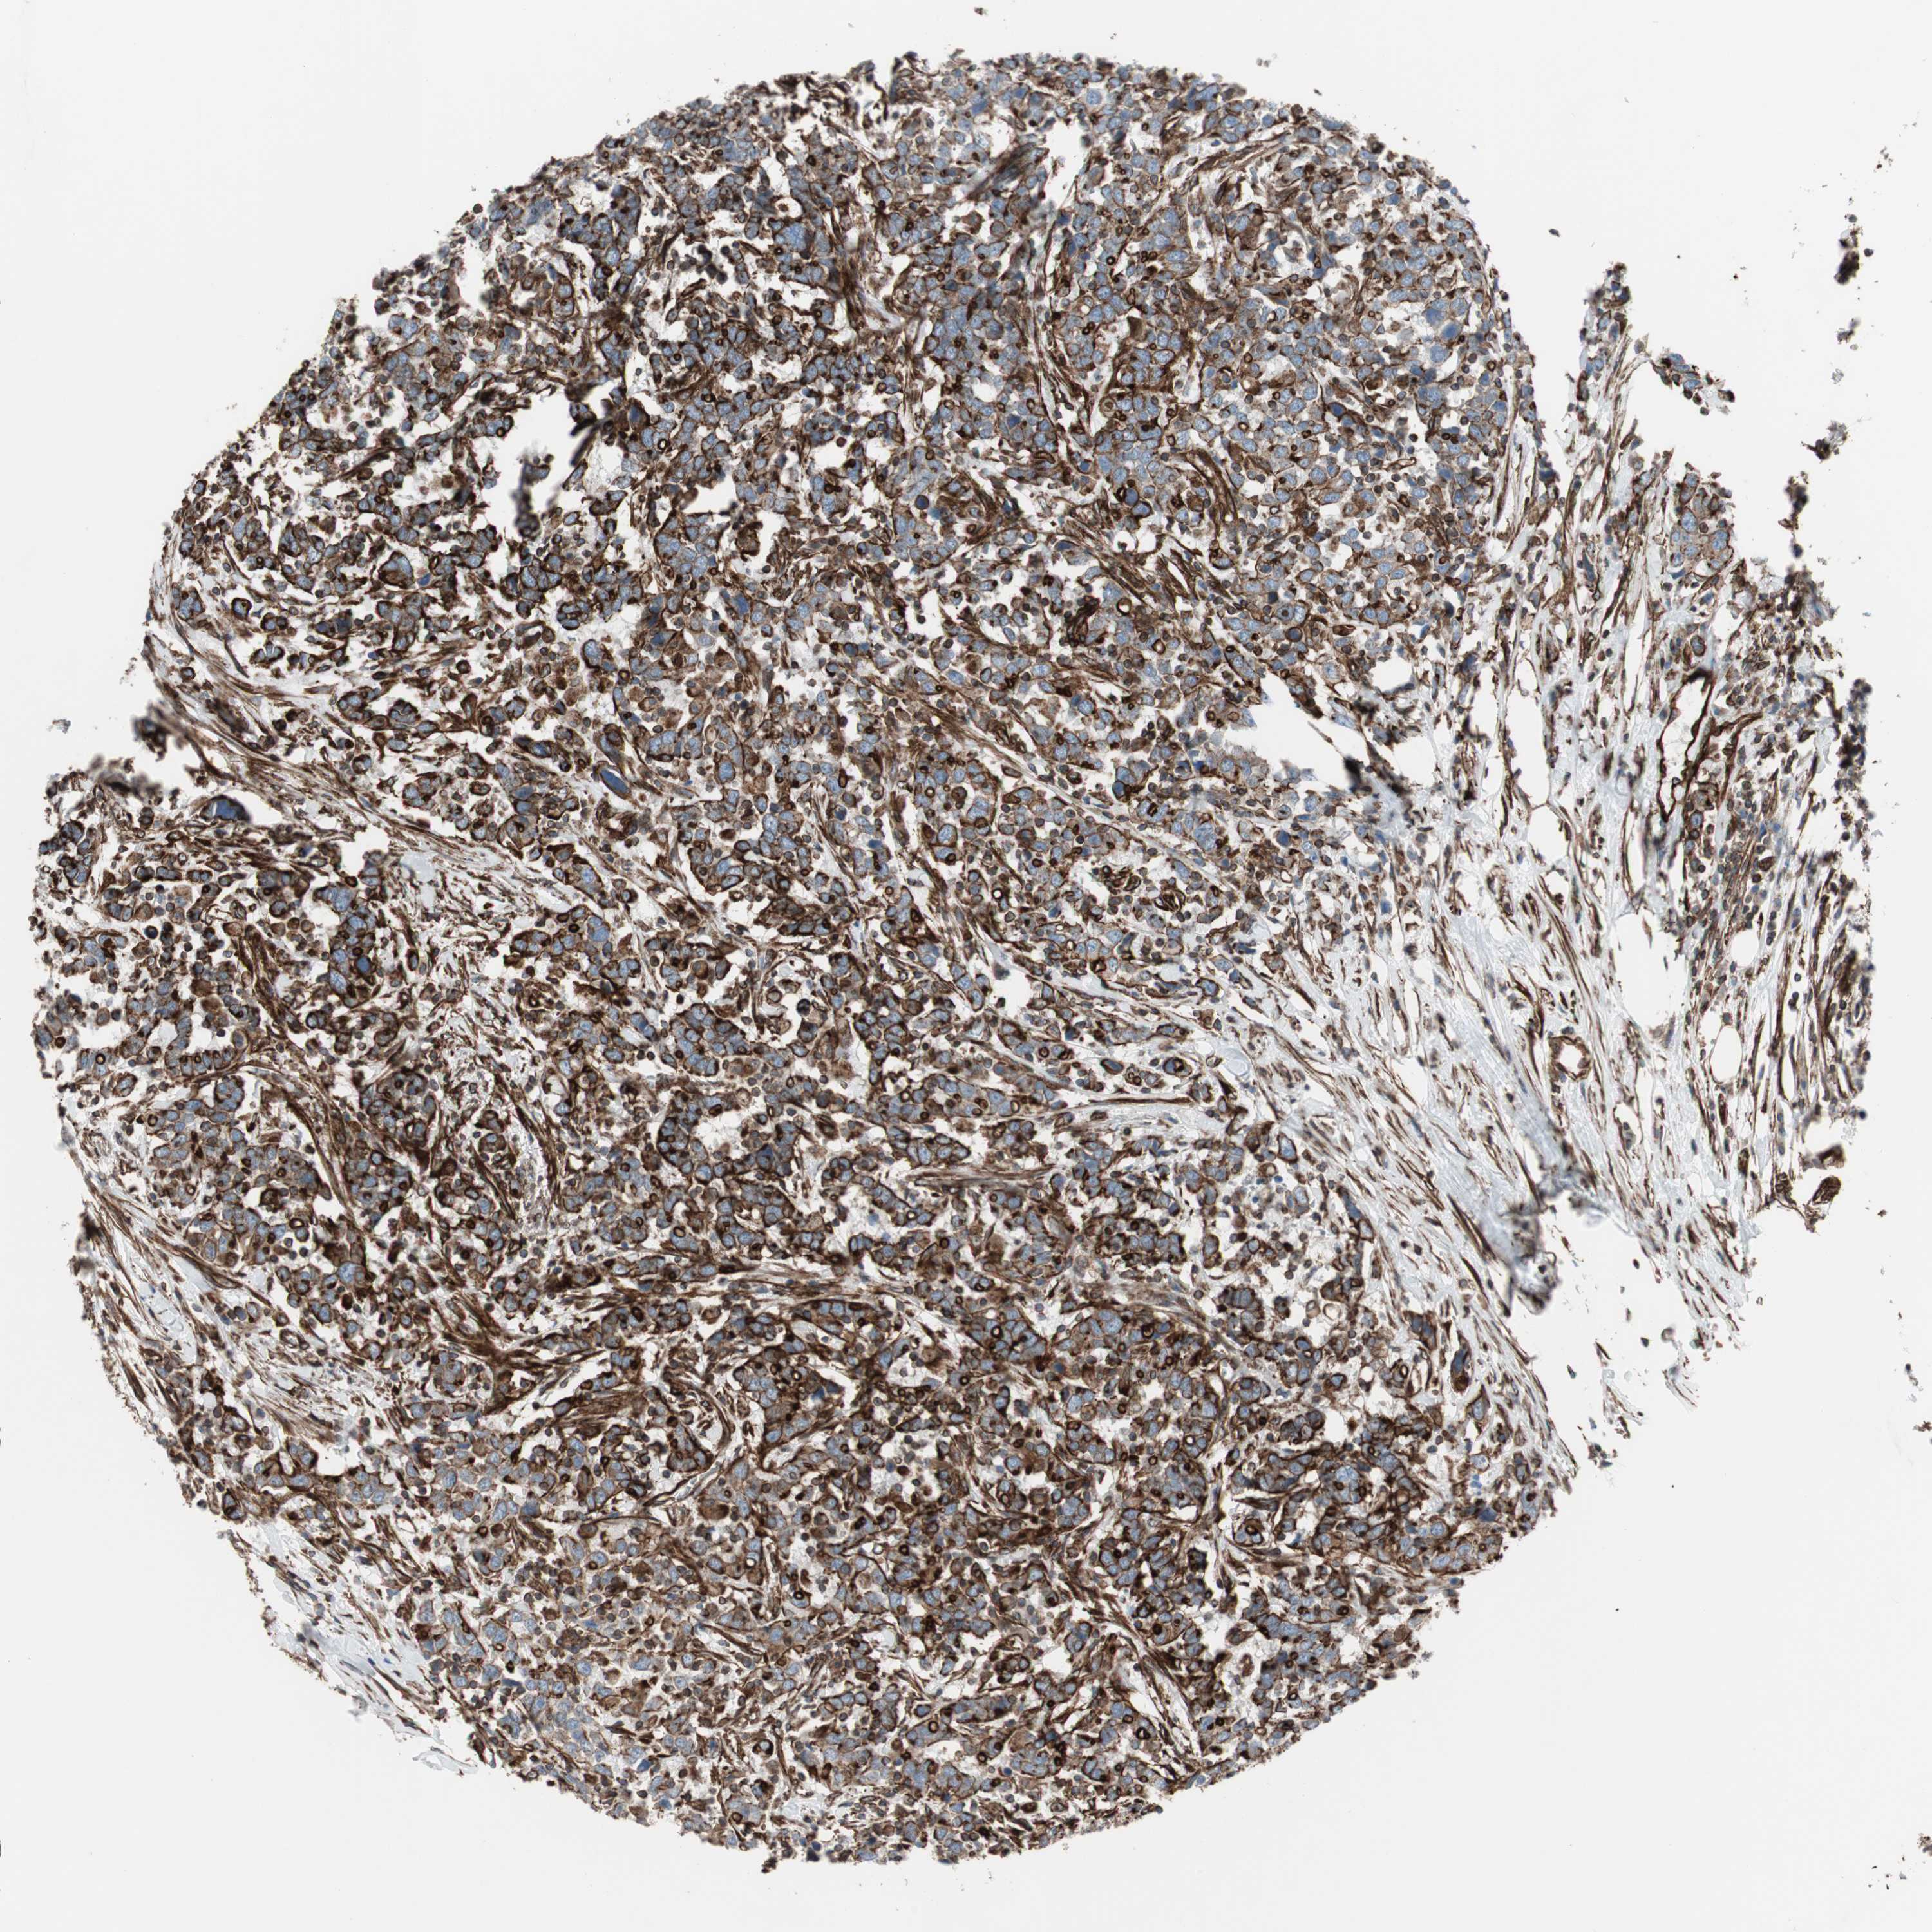

UROTHELIAL CANCER - Protein expressioni

A mouse-over function shows sample information and annotation data. Click on an image to view it in a full screen mode. Samples can be filtered based on level of antibody staining by selecting one or several of the following categories: high, medium, low and not detected. The assay and annotation is described here.

Note that samples used for immunohistochemistry by the Human Protein Atlas do not correspond to samples in the TCGA dataset.

Antibody stainingi

Antibody staining in the annotated cell types in the current human tissue is reported as not detected, low, medium, or high, based on conventional immunohistochemistry profiling in selected tissues. This score is based on the combination of the staining intensity and fraction of stained cells.

Each image is clickable and will lead to virtual microscopy that enables deeper exploration of all samples and also displays staining intensity scores, fraction scores and subcellular localization as well as patient and tissue information for each sample.

Antibody HPA007342

Staining

High

Medium

Low

Not detected

Intensity

Strong

Moderate

Weak

Negative

Quantity

>75%

75%-25%

<25%

None

Location

Nuclear

Cytoplasmic/membranous

Cytoplasmic/membranous,nuclear

Urothelial carcinoma, High grade

Urothelial carcinoma, Low grade